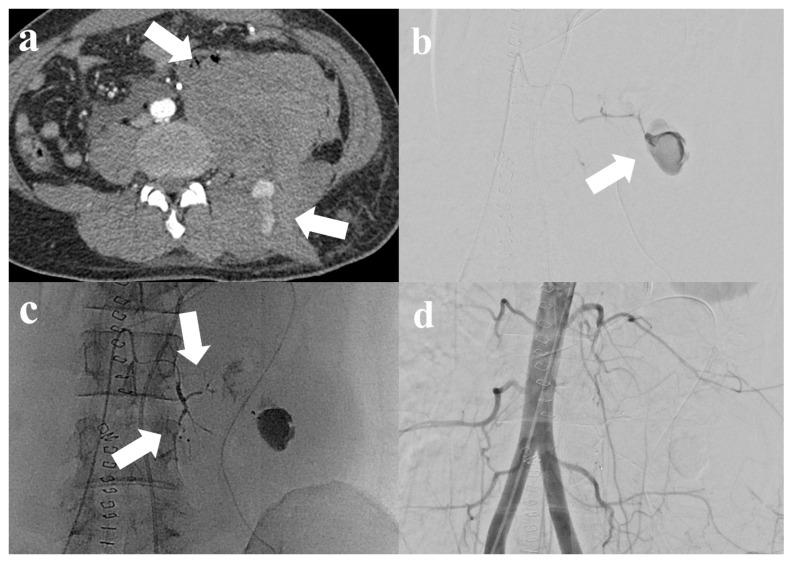

经导管动脉栓塞术治疗创伤性或自发性腰大肌及腹膜后出血患者的临床疗效与安全性

Clinical Outcomes and Safety of Transcatheter Arterial Embolization in Patients with Traumatic or Spontaneous Psoas and Retroperitoneal Hemorrhage.

We aimed to assess the effectiveness and safety of transcatheter arterial embolization (TAE) in the management of spontaneous or traumatic psoas and/or retroperitoneal hemorrhage. This single-center retrospective study enrolled 36 patients who underwent TAE for the treatment of psoas and/or retroperitoneal hemorrhage between May 2016 and February 2024. The patients' mean age was 61.3 years. The spontaneous group (SG, 47.1%) showed higher rates of anticoagulation therapy use compared with the trauma group (TG, 15.8%) ( = 0.042). The TG (94.7%) demonstrated higher survival rates compared with the SG (64.7%; = 0.023). Clinical failure was significantly associated with the liver cirrhosis ( = 0.001), prothrombin time ( = 0.004), and international normalized ratio ( = 0.007) in SG and pRBC transfusion ( = 0.008) in TG. Liver cirrhosis (OR (95% CI): 55.055 (2.439-1242.650), = 0.012) was the only identified independent risk factor for primary clinical failure in the multivariate logistic regression analysis. TAE was a safe and effective treatment for psoas and/or retroperitoneal hemorrhage, regardless of the cause of bleeding. However, liver cirrhosis or the need for massive transfusion due to hemorrhage increased the risk of clinical failure and mortality, necessitating aggressive monitoring and treatment.

摘要

我们旨在评估经导管动脉栓塞术(TAE)治疗自发性或创伤性腰大肌和/或腹膜后出血的有效性和安全性。这项单中心回顾性研究纳入了2016年5月至2024年2月期间接受TAE治疗腰大肌和/或腹膜后出血的36例患者。患者的平均年龄为61.3岁。与创伤组(TG,15.8%)相比,自发性组(SG,47.1%)抗凝治疗的使用率更高(P = 0.042)。与SG组(64.7%;P = 0.023)相比,TG组(94.7%)的生存率更高。临床失败与SG组的肝硬化(P = 0.001)、凝血酶原时间(P = 0.004)、国际标准化比值(P = 0.007)以及TG组的红细胞悬液输注(P = 0.008)显著相关。在多因素逻辑回归分析中,肝硬化(OR(95%CI):55.055(2.439 - 1242.650),P = 0.012)是唯一确定的原发性临床失败的独立危险因素。无论出血原因如何,TAE都是治疗腰大肌和/或腹膜后出血的安全有效方法。然而,肝硬化或因出血需要大量输血会增加临床失败和死亡的风险,需要积极监测和治疗。